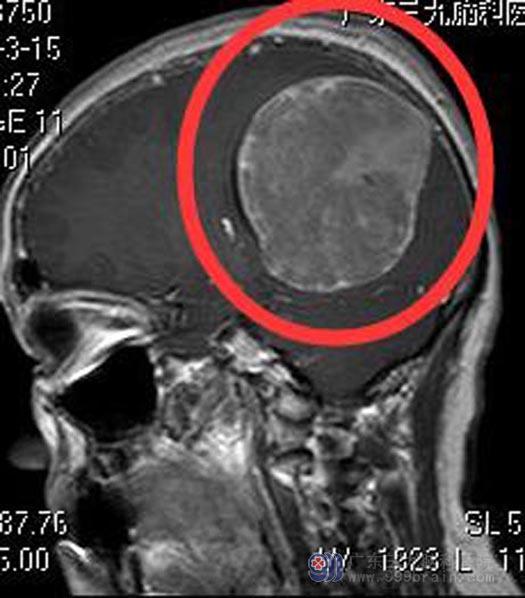

金姐六天前向左侧转头时出现头痛,以后枕部为主,休息后可缓解。当地医院头颅CT检查结果:右侧顶枕部巨大占位,考虑脑膜瘤。头颅MR检查提示:右侧枕顶部较大占位性病变,直径约7.2cm,考虑脑膜瘤可能性大。头颅CTA检查提示:右侧枕顶部占位性病变,血供丰富。

▲术前MR